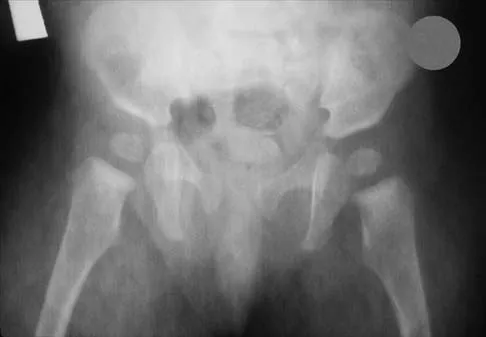

The mother of a 26-month-old boy reports that he has been unwilling to bear weight on his left lower extremity since he awoke this morning. She denies any history of trauma. He has a temperature of 99.4 degrees F (37.4 degrees C), and examination reveals that abduction of the left hip is limited to 30 degrees. Laboratory studies show a WBC of 11,000/mm3 and an erythrocyte sedimentation rate of 22 mm/h. A radiograph of the pelvis is shown in Figure 13. Management should consist of

Explanation

The most likely diagnosis is transient synovitis. Initial management should consist of bed rest and serial observation to rule out atypical septic arthritis of the hip. In an unreliable family situation, hospitalization for bed rest and observation may be indicated. Other disorders such as proximal femoral osteomyelitis, leukemia, juvenile rheumatoid arthritis, pelvic osteomyelitis, diskitis, and arthralgia secondary to other inflammatory disorders should be considered. However, these disorders are unlikely because of the paucity of abnormal clinical signs exhibited by the patient. On the other hand, transient synovitis of the hip in children is a diagnosis of exclusion; other possibilities should be explored if the patient's symptoms do not follow a typical course and resolve in 4 to 21 days.

References:

- Frymoyer JW (ed): Orthopaedic Knowledge Update 4. Rosemont, Ill, American Academy of Orthopaedic Surgeons, 1993, pp 505-513.